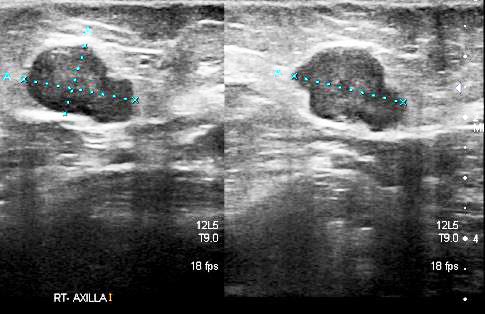

• USG.

Ultrasound Right Breast:

• A solid lesion with irregular margins seen at about 6 o’clock position (above) measuring about 2.9 x 2.7 x 2.7 cm. This is suspicious of a malignancy.

• There is a solid lobulated lesion measuring about 0.7 x 0.5 x 0.7 cm at about 2 o’clock position, about 1.8 cm from the nipple. this contains some calcifications.

• An enlarged right axillary node measuring 1.9 x 1.2 x 1.8 cm shows loss of normal fatty hilum (above). A few other smaller right axillary nodes also show loss of normal fatty hilum.

• An FDG-avid mass measuring 2.9 x 2.7 cm in the right breast.

• An FDG-avid right axillary node measures 1.8 x 1.3 cm. Small nodes are seen around this. No other FDG-avid axillary nodes seen.